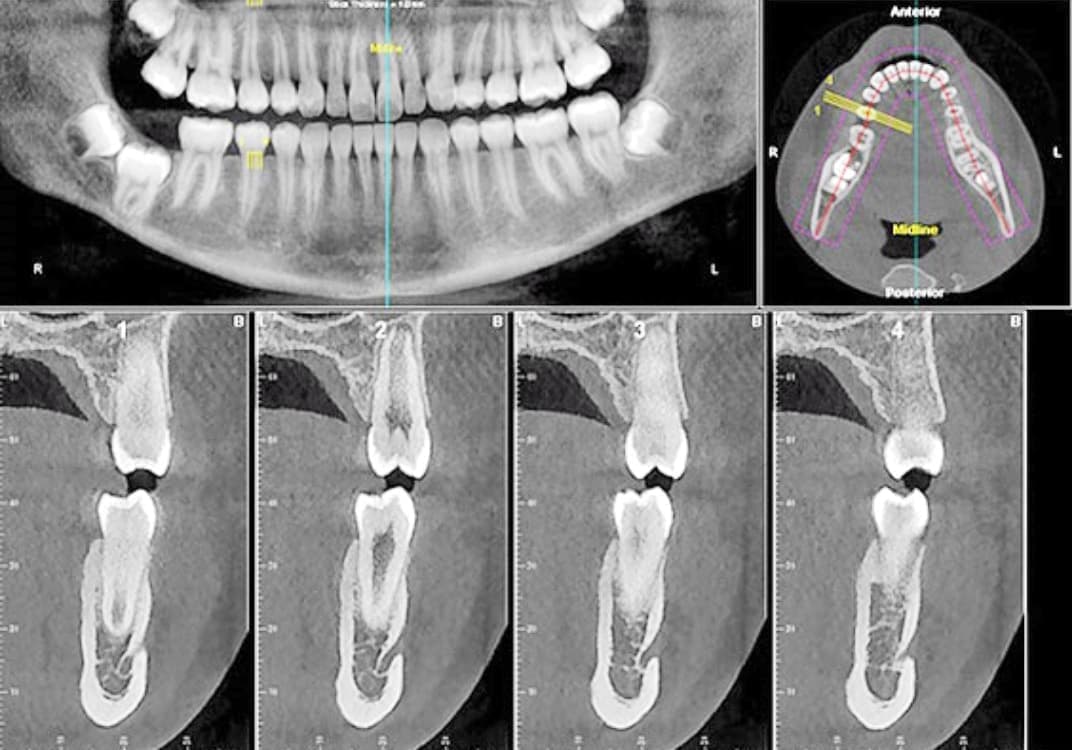

CT 3D デジタルレントゲン

PaX-i3D CT Roentgen

高精細で被爆量も少なく安心

当院では、歯科用CT3Dデジタルレントゲンを活用し、身体への負担を少なく、状況を詳しく把握し、的確な治療を提供出来るよう心掛けております。

CTデジタルレントゲンに使われているX線センサーは高感度で照射時間も短く、より低線量でのレントゲン画像の取得が可能となり、お子様にも安心です。

インプラント手術や歯周病治療、歯の根の病気に関係する治療の正確な診断、治療計画には、CTによる撮影が欠かせません。

例えば、親知らずの抜歯や骨内に埋伏している過剰歯の抜歯等、正確な位置や神経や血管等との距離を3次元的に把握することで負担の少ない安心な処置が行えます。